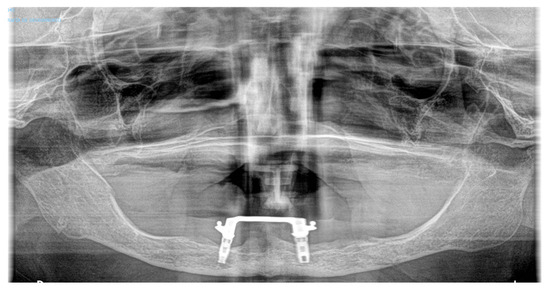

3.1. Case 1

3.2. Case 2